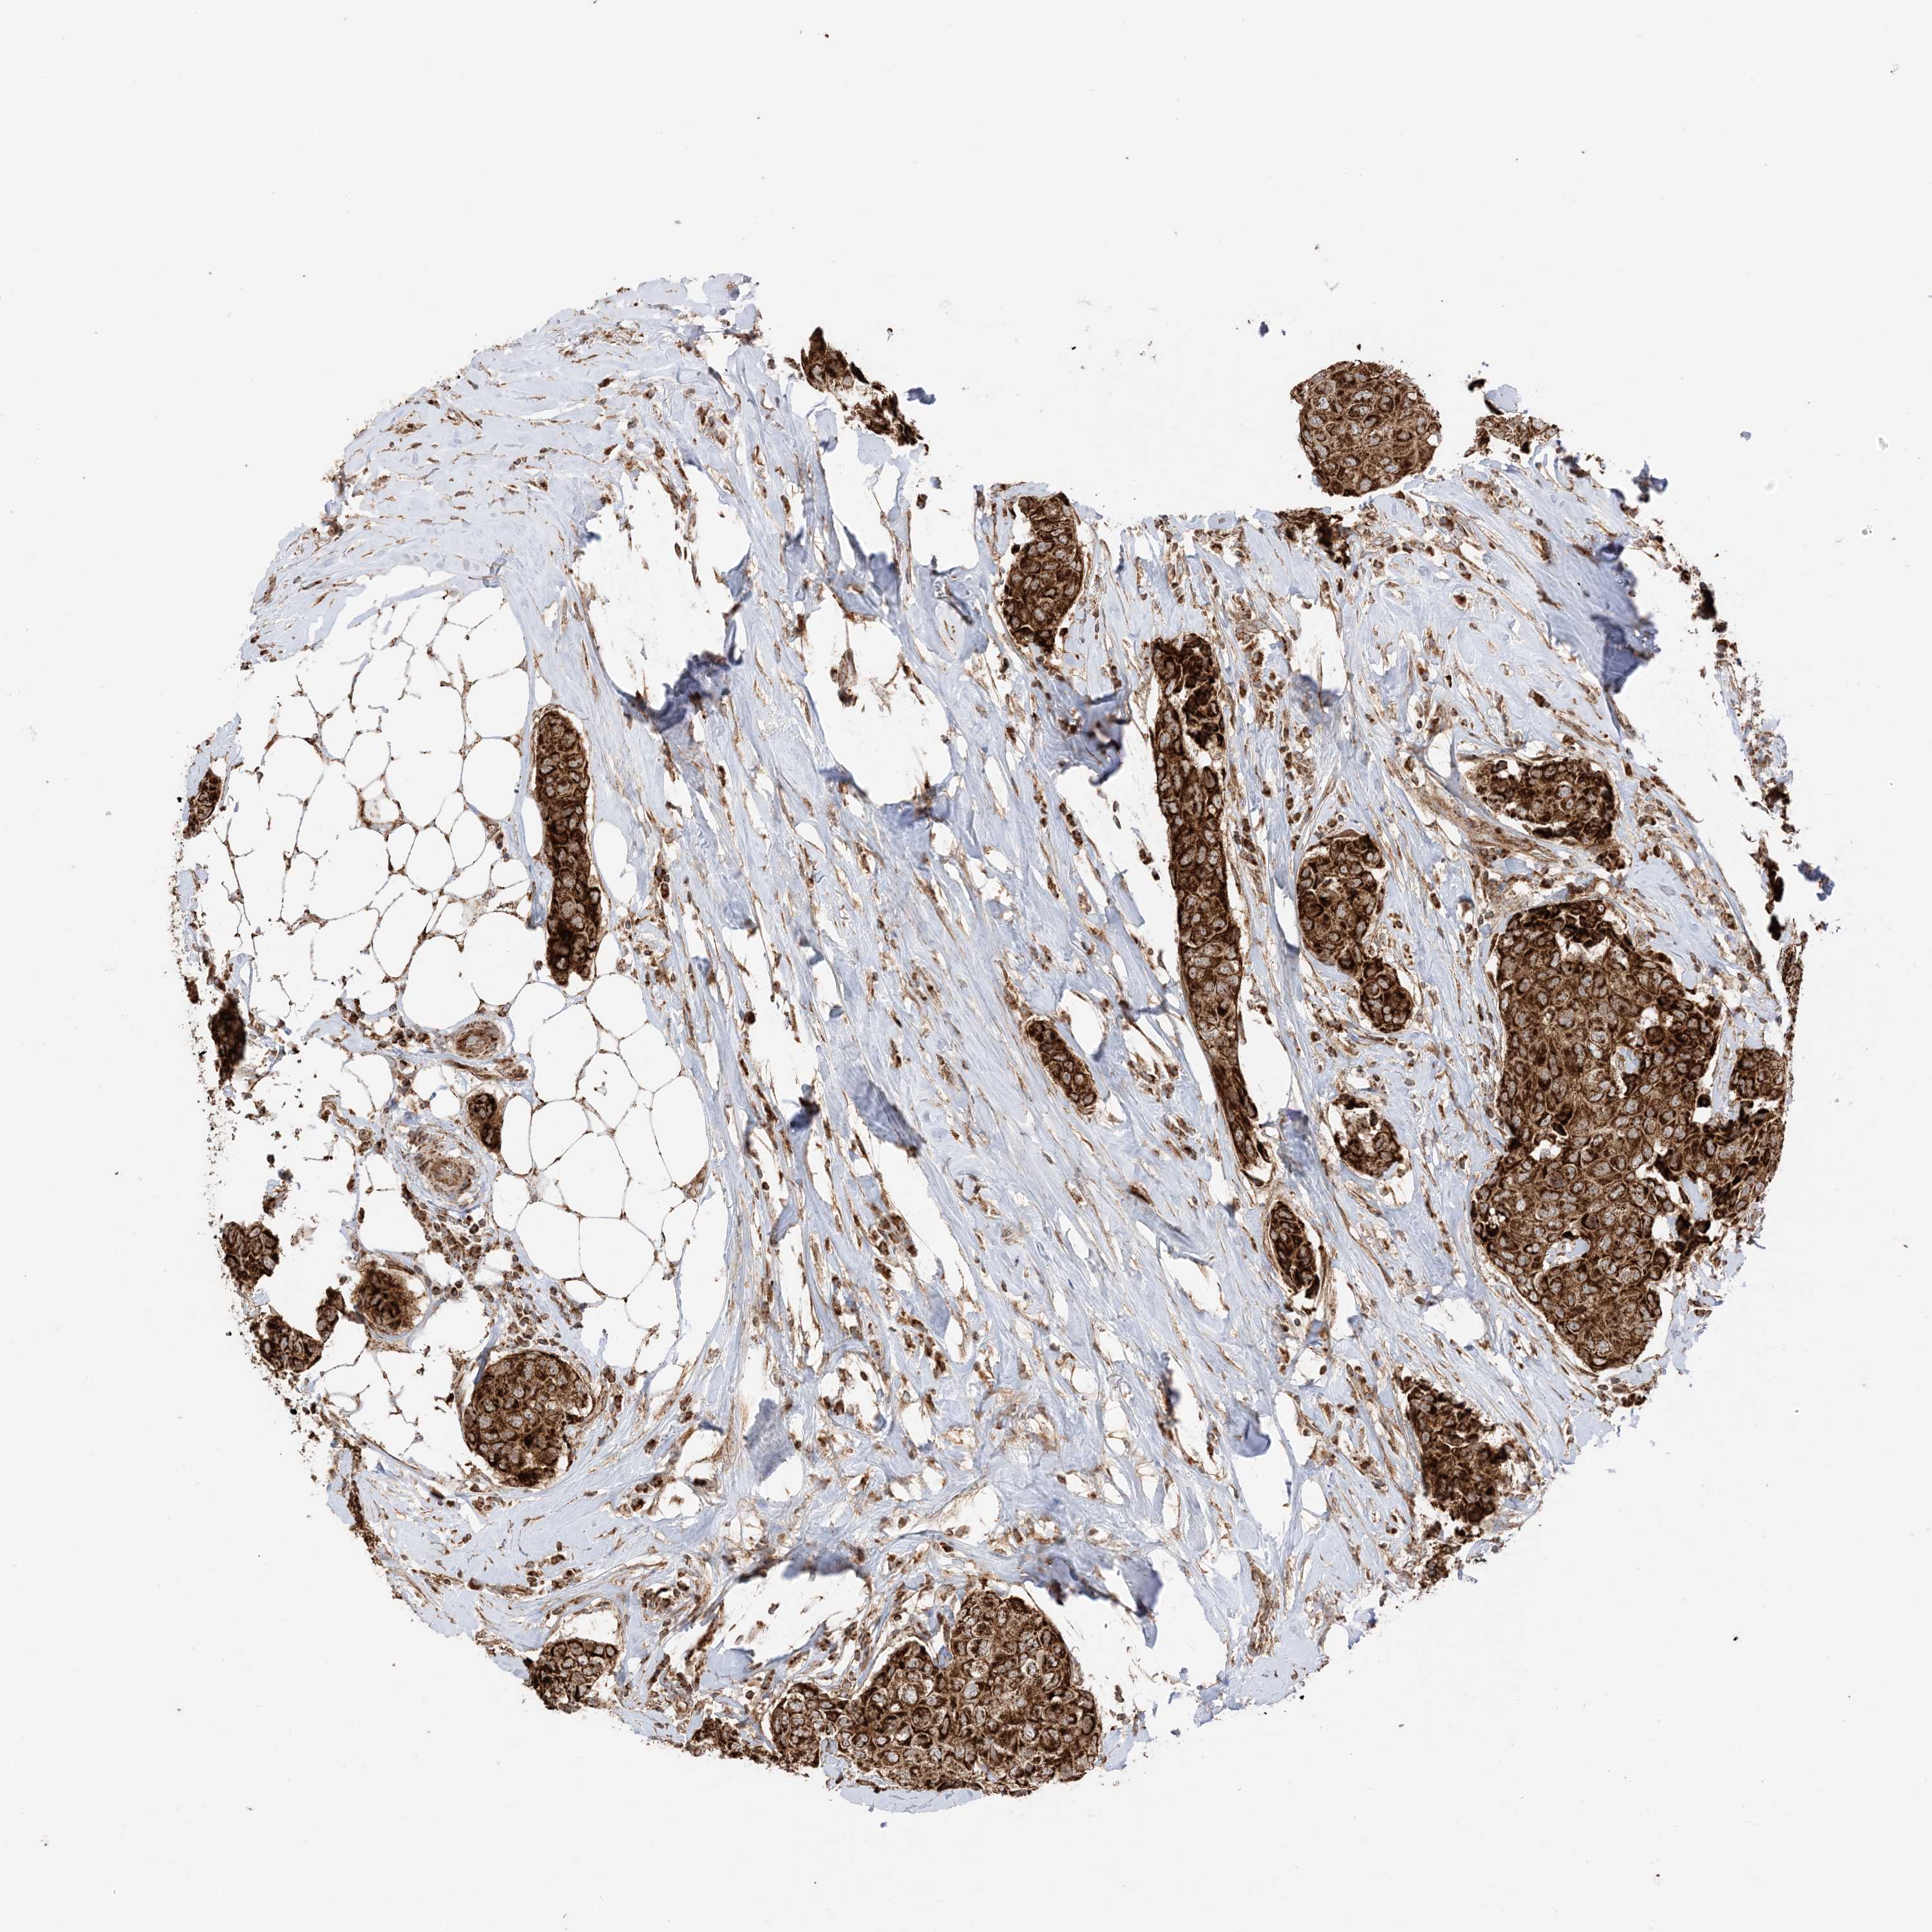

CANCER BREAST CANCER Show tissue menu

BRCA TCGA BRCA VALIDATION PROTEIN EXPRESSION